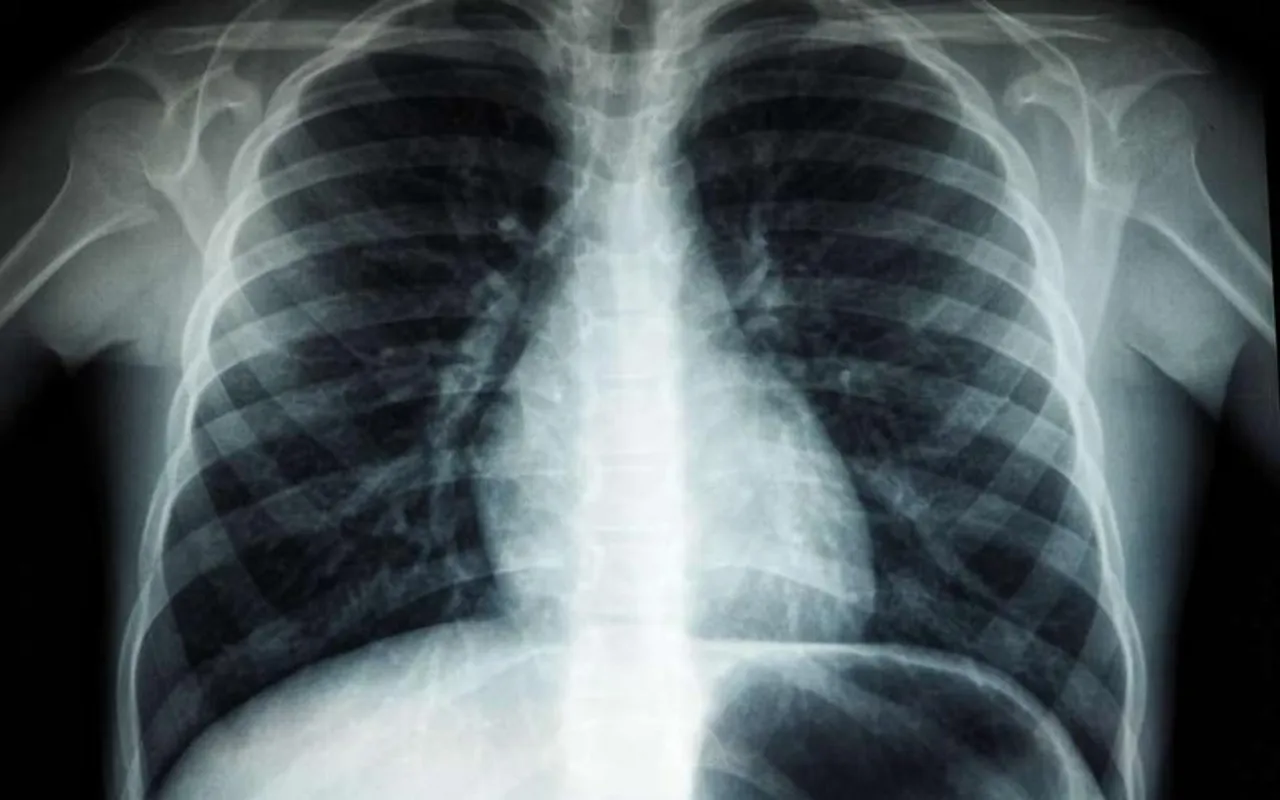

A study has been published in the Lancet Healthy Longevity Journal. It explores the emergence of a new technology which predicts a person’s age based on data made available through the person’s chest X-ray scans.

The principle of Deep Neural Networks is behind the estimation of age. Ageing causes changes in the radiological findings of the chest X-rays. The artificial intelligence is provided with just the data of frontal view chest X-rays.

2 substantially large data sets were fed to the artificial intelligence. One with healthy individuals who went through routine check ups between 2008 and 2021. Another subset contained data from individuals with a history of ailments from across 5 different health institutes across Japan.

In healthy individuals the X-ray estimated age would be very close to their actual age. If there is a difference in the 2 with age estimation obtained through chest X-rays being on the higher side it is also indicative of the fact that the individual might be susceptible to chronic illnesses such as hypertension and chronic obstructive pulmonary disease. Therefore, through this technology individuals who have greater risks could be identified at an early age and hence early intervention could prove to be decisive to prevent complications.